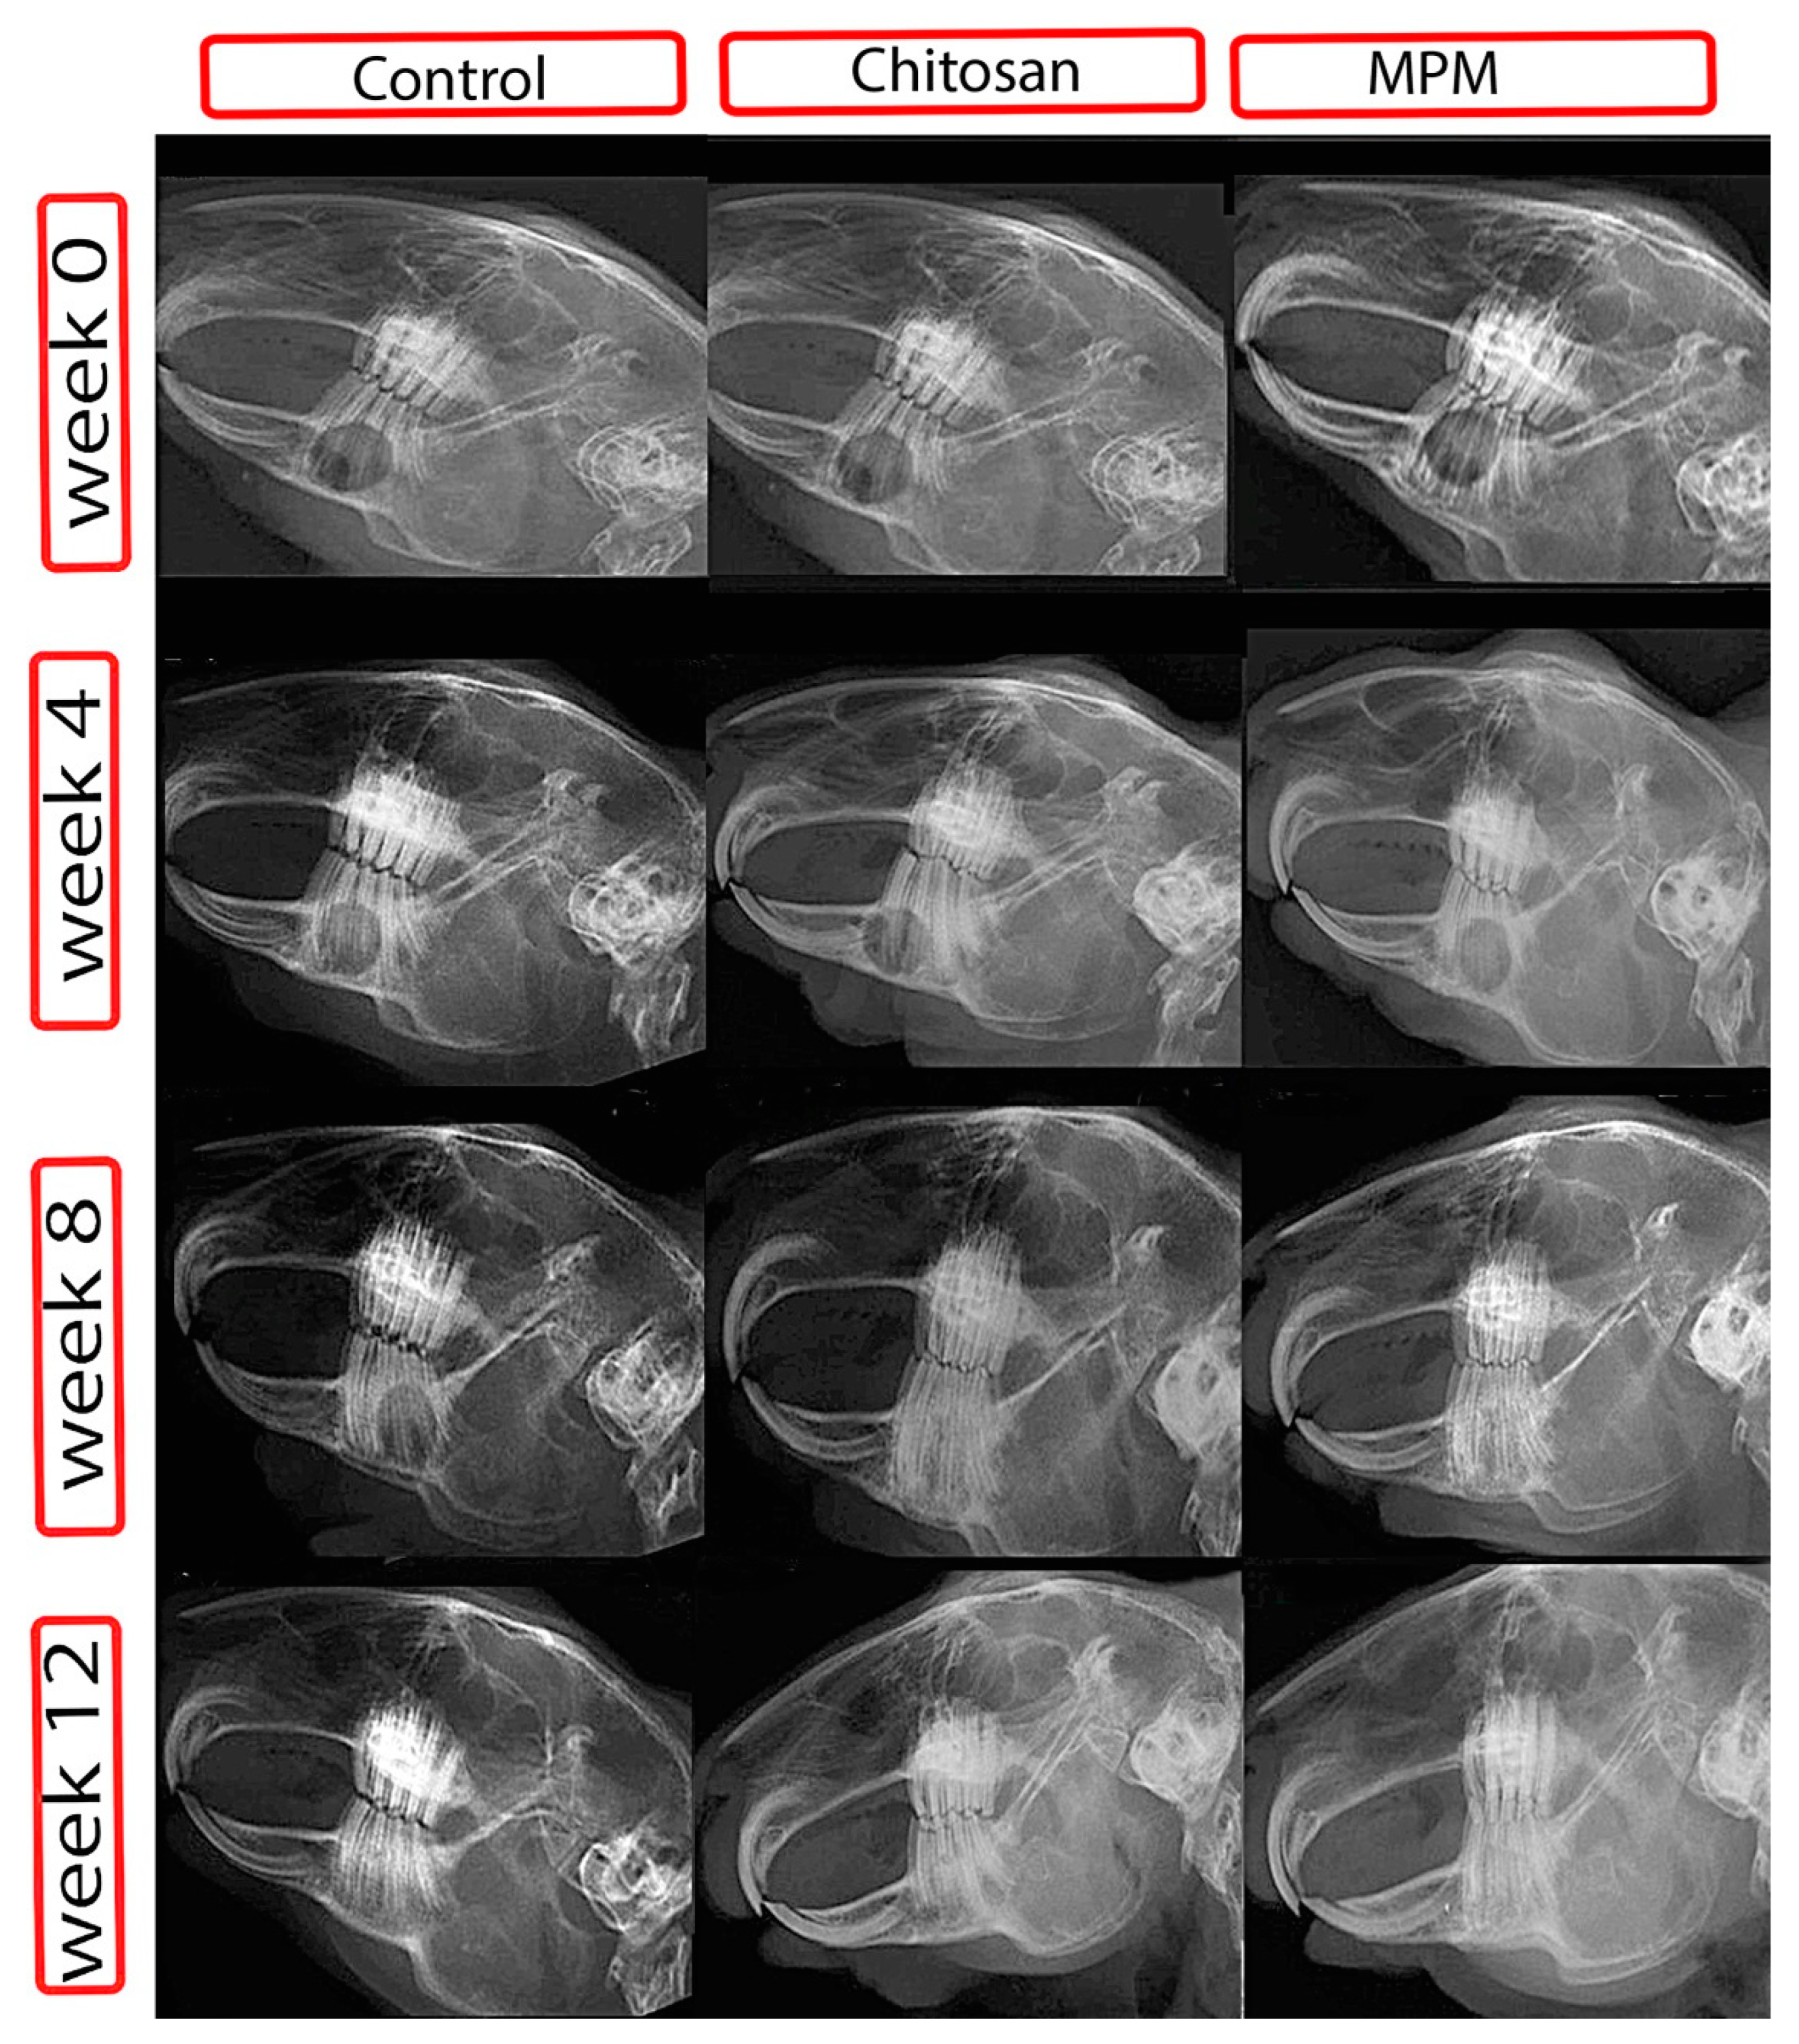

3.2. Radiographic Findings